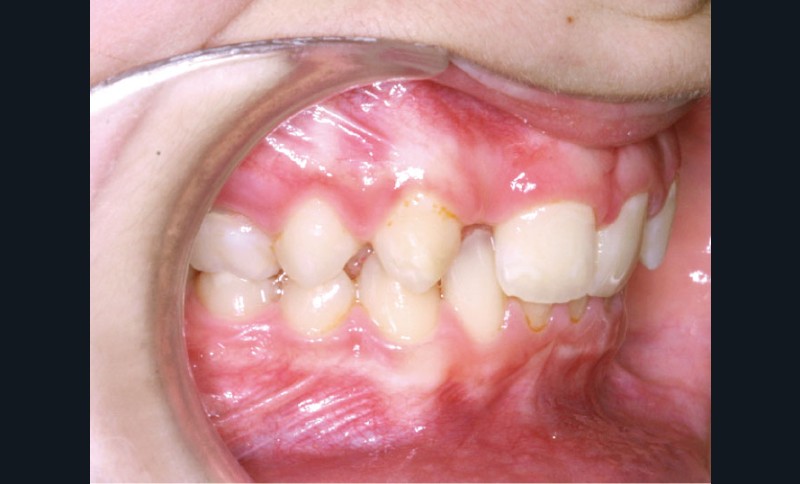

Ludivine T. âgée de 12 ans et demi présente une agénésie des deux incisives latérales maxillaires dans un contexte occlusal de classe II division 2 (fig. 1 à 3).

L’examen clinique exo-buccal révèle un visage équilibré en classe I squelettique tendance hypodivergente. De profil, le menton est marqué et le profil sous nasal très légèrement concave (fig. 1).

Les vues endo-buccales (fig. 2) montrent la classe II division 2 occlusale associée à une forte supraclusion incisive et l’évolution spontanée de 13 et 23 pratiquement en place de 12 et 22. Il persiste cependant un diastème disgracieux entre 13 et 11.